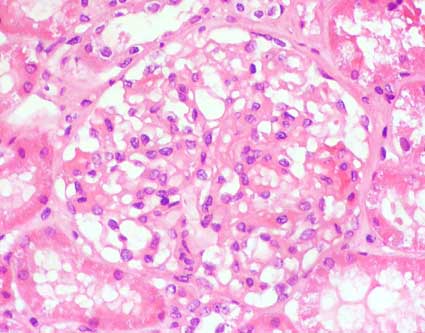

Figure 1.

Mild mesangial cell proliferation: >3 nuclei/mesangial area (H&E,

X400).